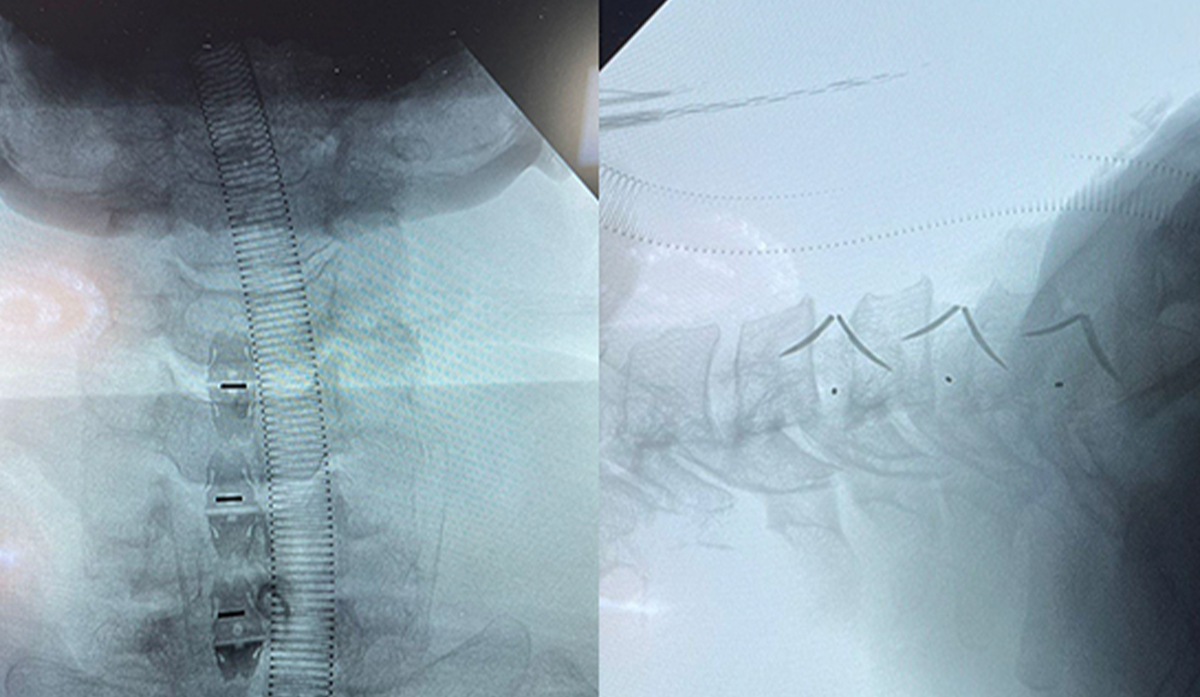

• Edistynyt kohdunkaulan fuusiokirurgia Meksikossa Uni-C:n erillishäkin avulla | CZMEDITECH Spine Technology

Tämä kliininen tapaustutkimus esittelee onnistuneen kohdunkaulan fuusioleikkauksen, joka tehtiin Meksikossa käyttämällä CZMEDITECHin Uni-C itsenäistä kohdunkaulan häkkiä. 53-vuotiaalle potilaalle, jolla oli kohdunkaulan välilevytyrä ja takaosan pitkittäisen nivelsiteen luutuminen, tehtiin minimaalisesti invasiivinen fuusio tohtori Octavio Villasana Ramosin ohjauksessa. Toimenpide saavutti vakaan kiinnityksen ja nopean leikkauksen jälkeisen toipumisen. Uni-C-erillinen häkki, joka on suunniteltu korkealle ja matalalle kohdunkaulan tasolle, yksinkertaistaa implantaatiota, vähentää kirurgin väsymystä ja varmistaa pitkän aikavälin vakauden. Tämä tapaus osoittaa CZMEDITECHin edistyneen selkärangan teknologian ja sen kasvavan käytön maailmanlaajuisessa selkäkirurgiassa. Lue lisää